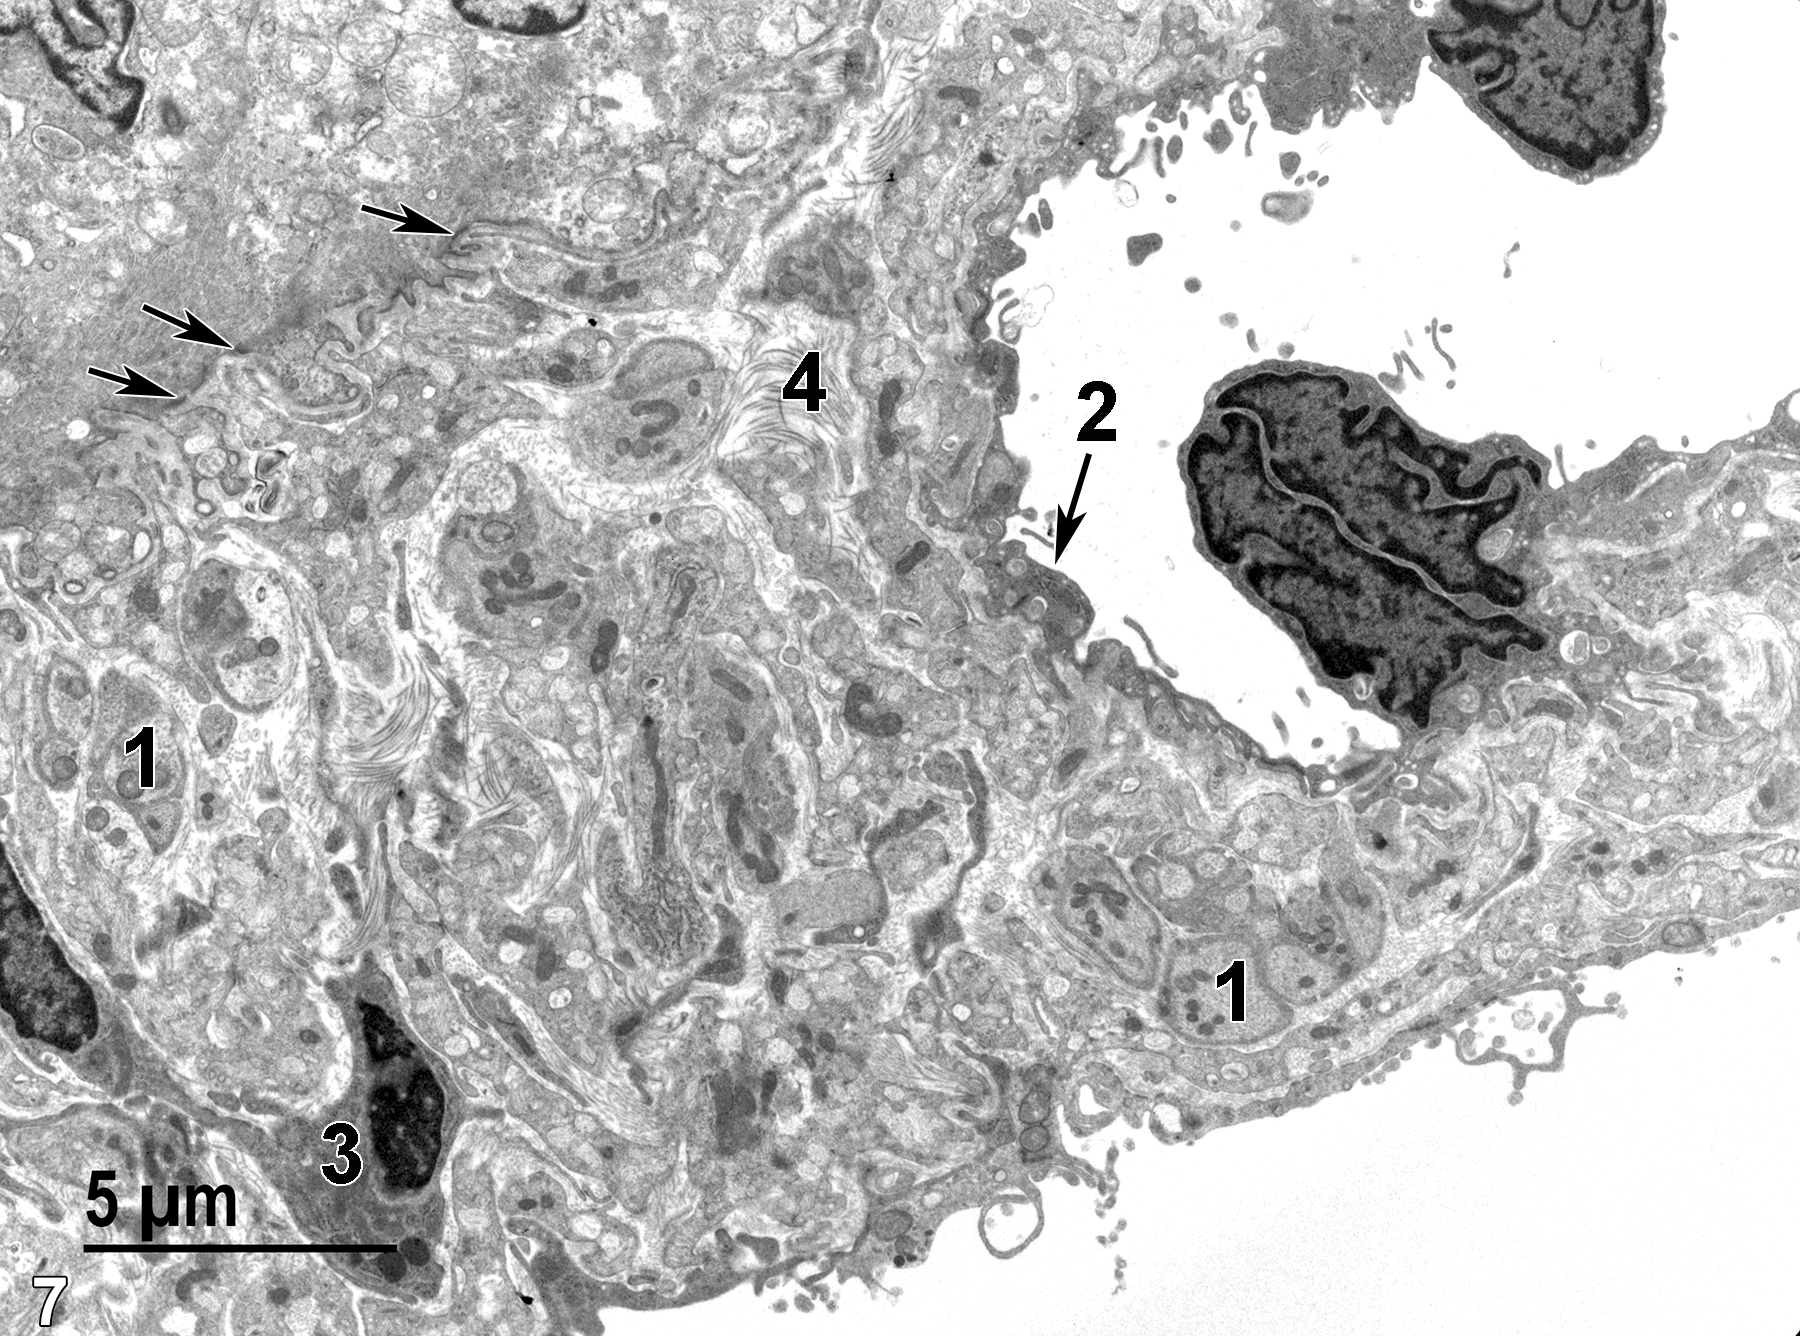

The eye consists of an anterior portion that captures light (cornea and pupil), regulates light (iris and ciliary body), and focuses the light on the retina (lens). The posterior aspect of the eye consists of the retina, which has ten layers, including photoreceptors (rods and cones) that are stimulated by light and nerve cells that conduct signals to the optic nerve and from there to the brain.